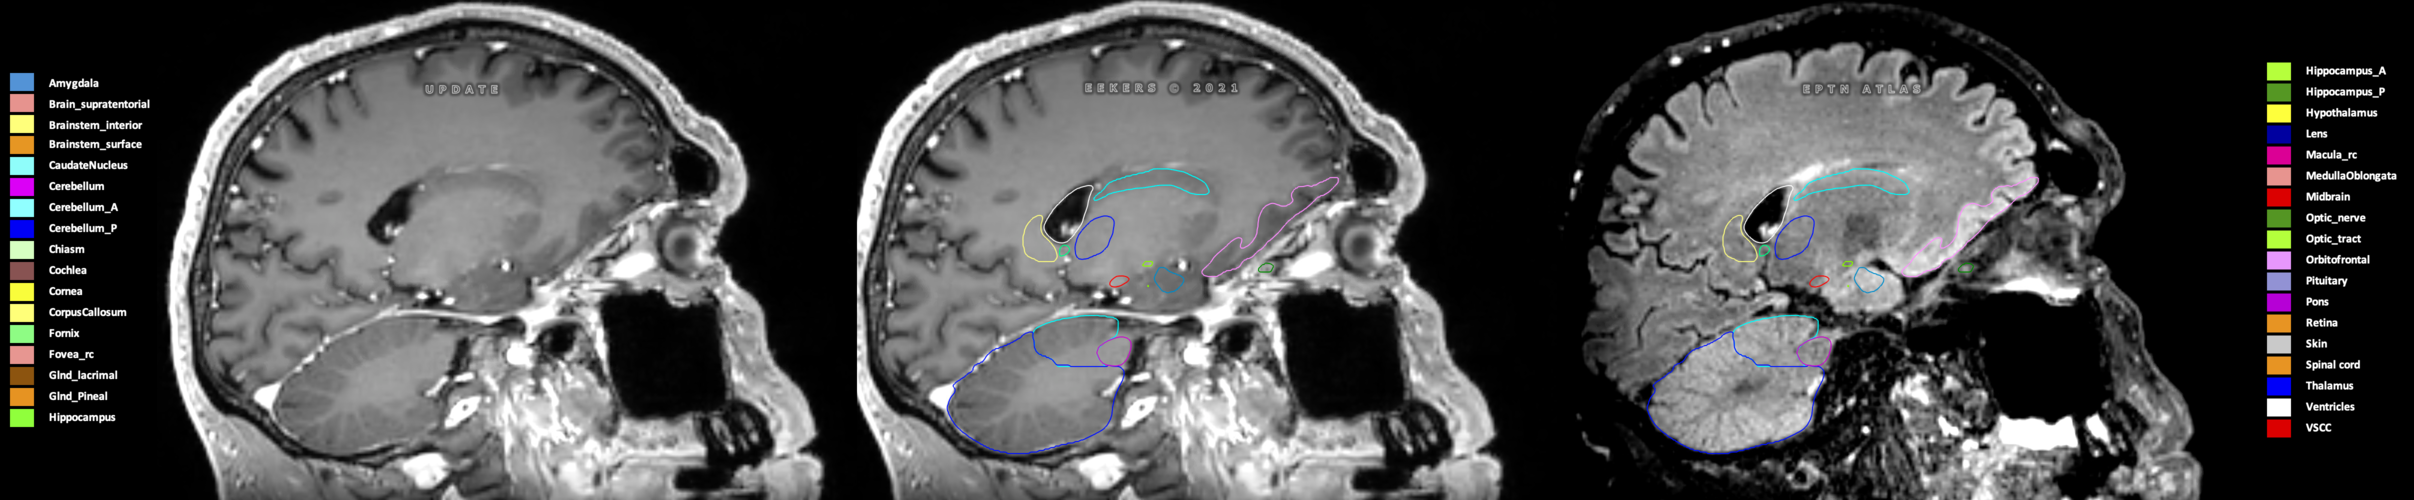

Included are all OARs known to be relevant for radiation-induced toxicity in neuro-oncology: brain, brainstem (midbrain, pons, medulla oblongata), chiasm, cerebellum (anterior & posterior), cochlea, cornea, hippocampus (anterior & posterior), hypothalamus, lens, lacrimal gland, optic nerve, pituitary, skin, and vestibular & semicircular canals. To further facilitate research on cognition, vision and radiological changes after irradiation of the brain, potential clinically-relevant OARs are included: amygdala, caudate nucleus, cerebellum (anterior & posterior), corpus callosum, fornix, macula, optic tract, orbitofrontal cortex, periventricular space (PVS), pineal gland, and thalamus.

Three-dimensional delineation of the 25 consensus OARs for neuro-oncology are shown on CT (WW/WL 120/40, 3000/600), 3T MR images, (T1Gd, T2FLAIR 1mm) and 7T MR (MP2RAGE 0.7 mm). All are presented in transversal, sagittal and coronal view.